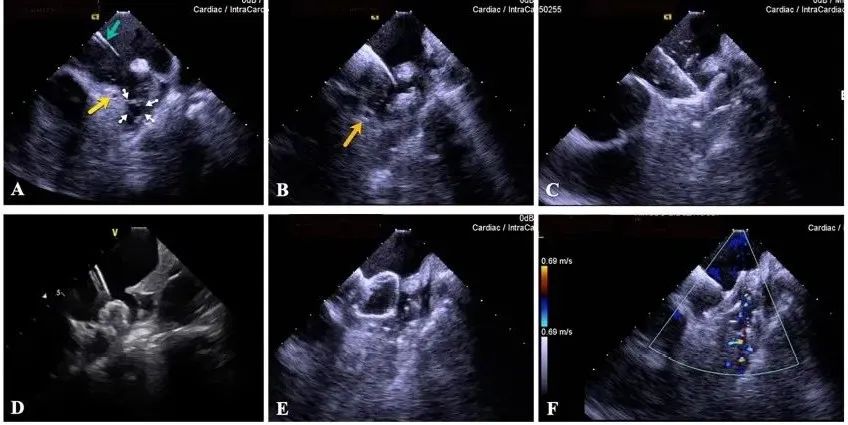

一種與心導(dǎo)管檢查相結(jié)合的超聲心動圖診斷新興技術(shù),通過將超聲探頭置于心腔內(nèi)部,發(fā)射并接收超聲信號,來精確獲取心臟解剖結(jié)構(gòu)、心臟血流動力學(xué)等信息的實時成像。與其他影像技術(shù)相比,ICE技術(shù)具有操作簡單、無輻射、安全性高、手術(shù)效率高、實用等優(yōu)勢,ICE在很大程度上有望取代經(jīng)食道超聲心動圖(TEE),成為電生理和結(jié)構(gòu)性心臟病領(lǐng)域的理想成像方式。

目前ICE技術(shù)已被應(yīng)用于左心耳封堵、房顫射頻消融、二尖瓣成形、房間隔缺損封堵等多種心臟介入手術(shù),應(yīng)用場景主要圍繞臟電生理、結(jié)構(gòu)性心臟病等領(lǐng)域,目前以電生理應(yīng)用為主。數(shù)據(jù)顯示,我國結(jié)構(gòu)性心臟病介入器械市場規(guī)模已從2017年的4億元增長至2021年的20億元,年復(fù)合增長率達48.3%;預(yù)計到2025年,該市場規(guī)模將達到104億元,可以預(yù)見ICE市場規(guī)模也將同步高速增長,未來市場發(fā)展空間廣闊。

心腔內(nèi)超聲(ICE)技術(shù)壁壘極高,國內(nèi)主要廠商核心部件仍舊為進口,集成了超聲和圖像處理最前端技術(shù),包括超聲探頭、線纜、軟件成像算法等,是當前內(nèi)窺超聲方向最具挑戰(zhàn)的領(lǐng)域。ICE的應(yīng)用經(jīng)歷了2D平面成像、3D三維立體成像、以及4D的實時三維立體成像階段。